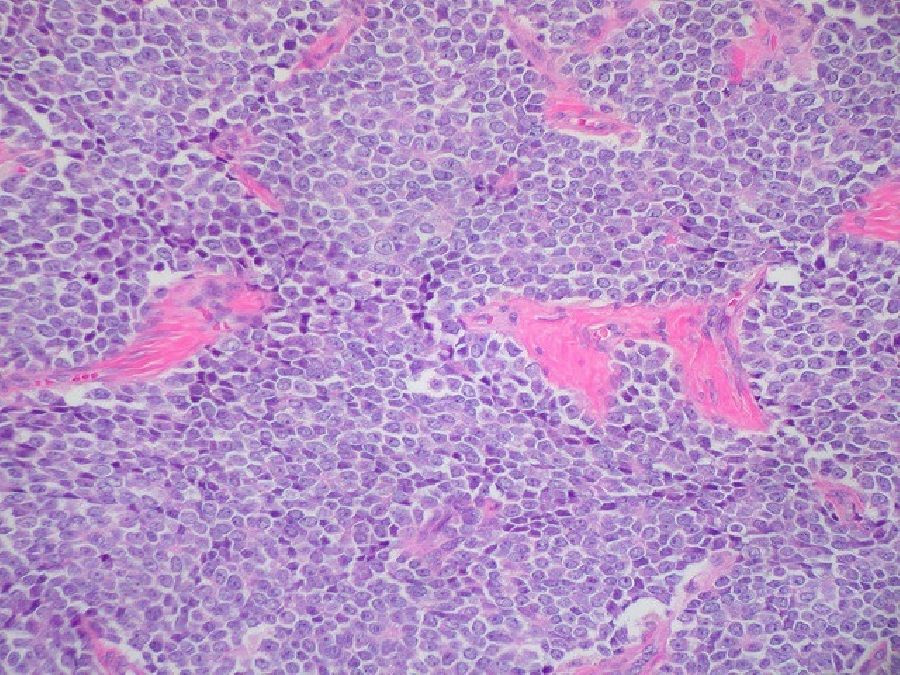

A pesar del tratamiento intensivo, los tumores sólidos de alto riesgo como el neuroblastoma, el sarcoma de Ewing y el rabdomiosarcoma son difíciles de curar porque la enfermedad en esos pacientes de alto riesgo no responde a la terapia.

Los investigadores probaron su profármaco en varios modelos de enfermedad en ratones, incluido el neuroblastoma con resistencia a los medicamentos tanto intrínseca como adquirida, un sarcoma de Ewing quimiorresistente y un rabdomiosarcoma con fusión positiva.